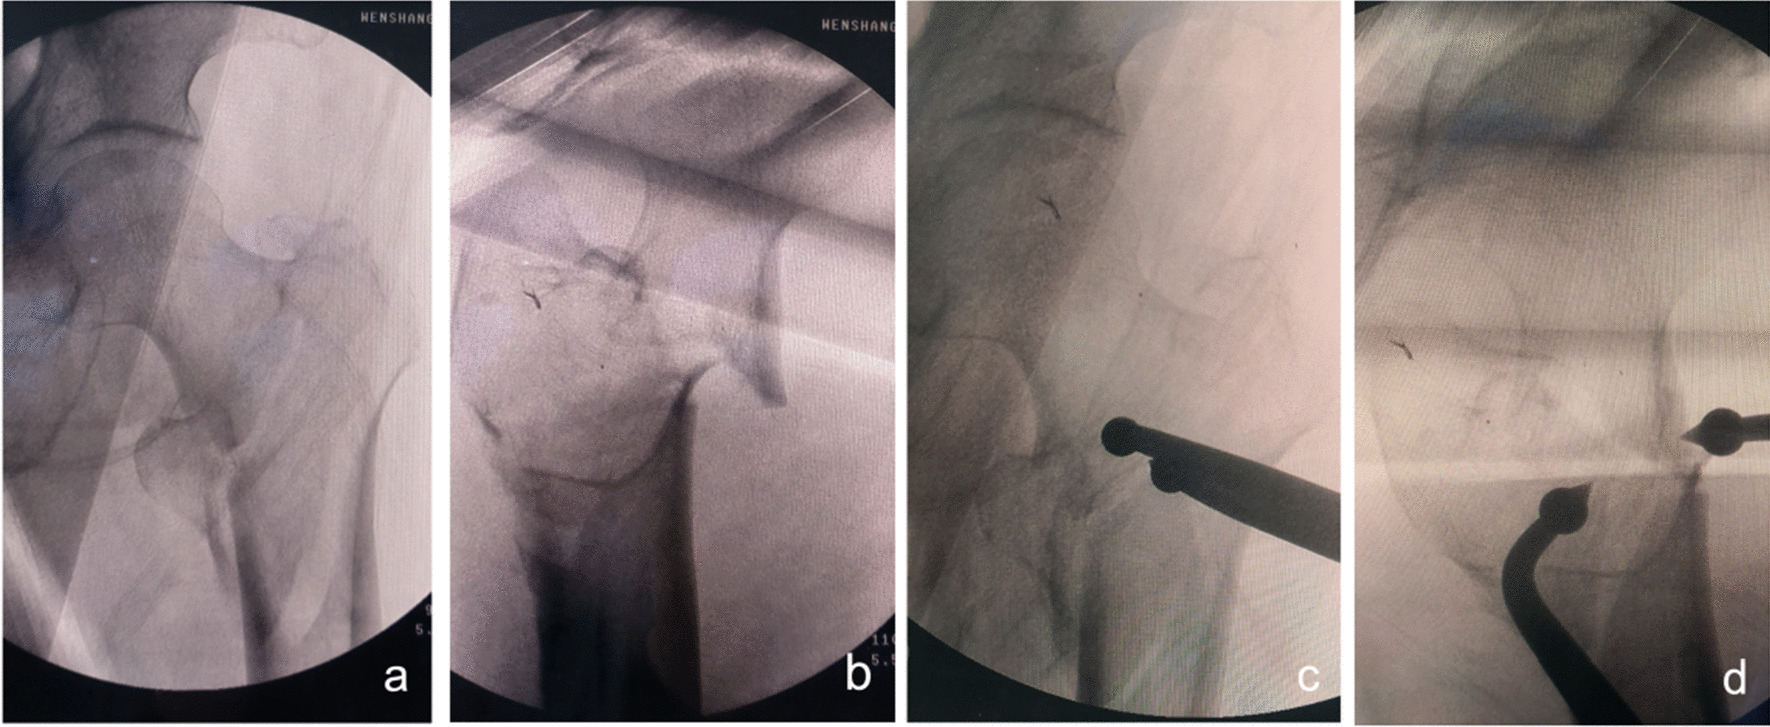

Fig. 3.

Anteroposterior and lateral X-ray films before and after reduction in patients with difficulty in reduction on the sagittal plane and pronation displacement of the proximal fracture segment a, b Before reduction; c, d After reduction (one head placed in front of the proximal fracture segment and the other head behind the greater trochanter)

Fig. 4.

Anteroposterior and lateral X-ray films before and after reduction in patients with difficulty in reduction on the sagittal plane and supination displacement of the proximal fracture segment a, b Before reduction; c, d After reduction